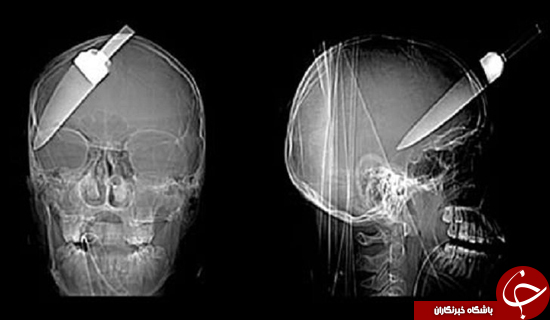

باورنکردنیترین اشیا در بدن انسان+تصاویر

اکسریهای زیر واقعا دیوانه کننده به نظر میآیند اما مطمئن باشد که واقعی هستند. ۱٫ میخ ۴ اینچی: پاتریک لولر از درد دندانش ناله میکرد اما زمان زیادی نگذشت تا دندانپزشکش متوجه موضوع شود. میخ ۴ اینچی که در سقف دهان این کارگر بود همه چیز را روشن کرد. ۲٫ قیچی قورت داده شده: این […]...